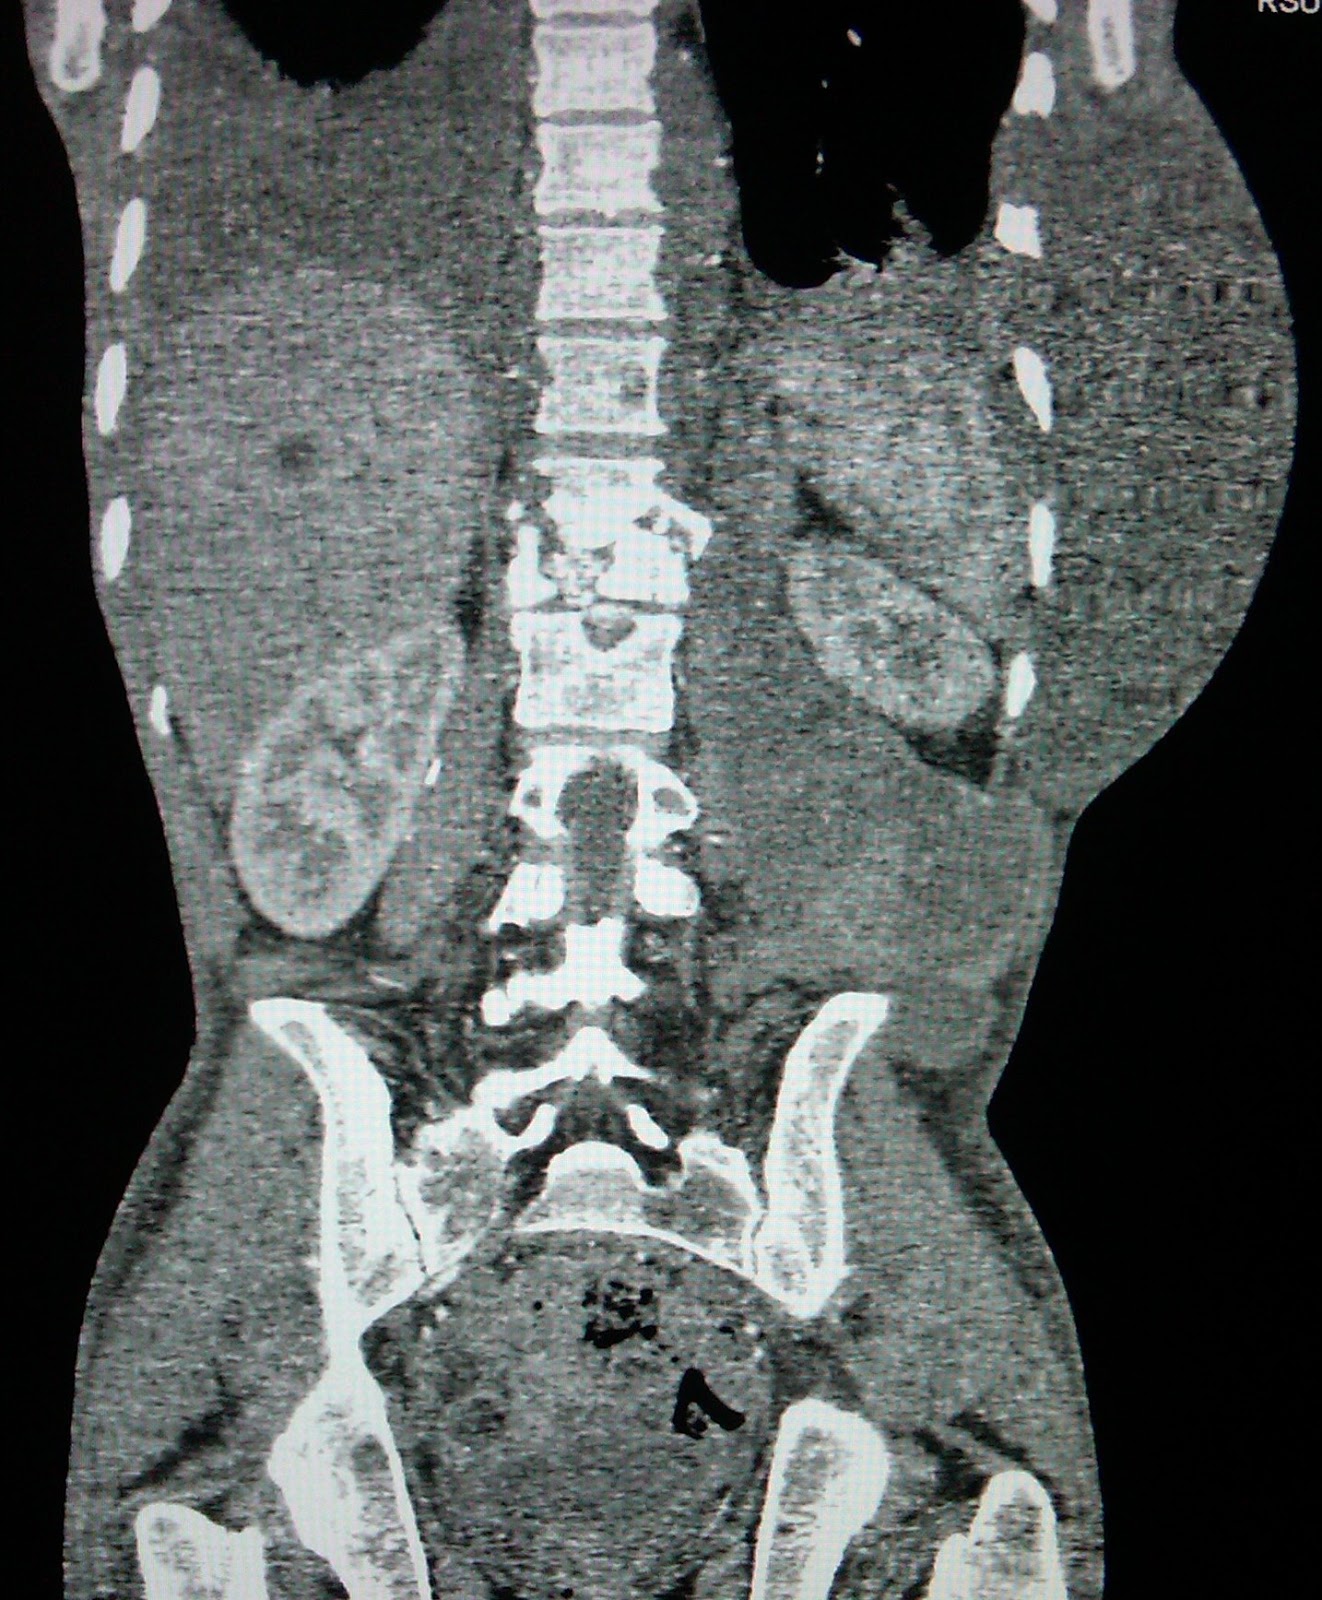

Spondylitis TB with Paravetebral soft tissue abses

Male 26 year old , with clinical information back pain , paraparese inferior and abdominal wall tumor

From MSCT Scan thoraxoabdominal :

There is destruction anterior part of the superior end plate V. Lumbal 1 and inferior end plate V.thoracal 12 ,with acute angulation that retropultion to the central canal and make kipotic angle , with paravetebral , left psoas until subcutan mass with rim contras enchancement

Conclusion :

Spondylitis TB at level V Th 12-V L 1 with paravetebral , psoas and subcutan abses